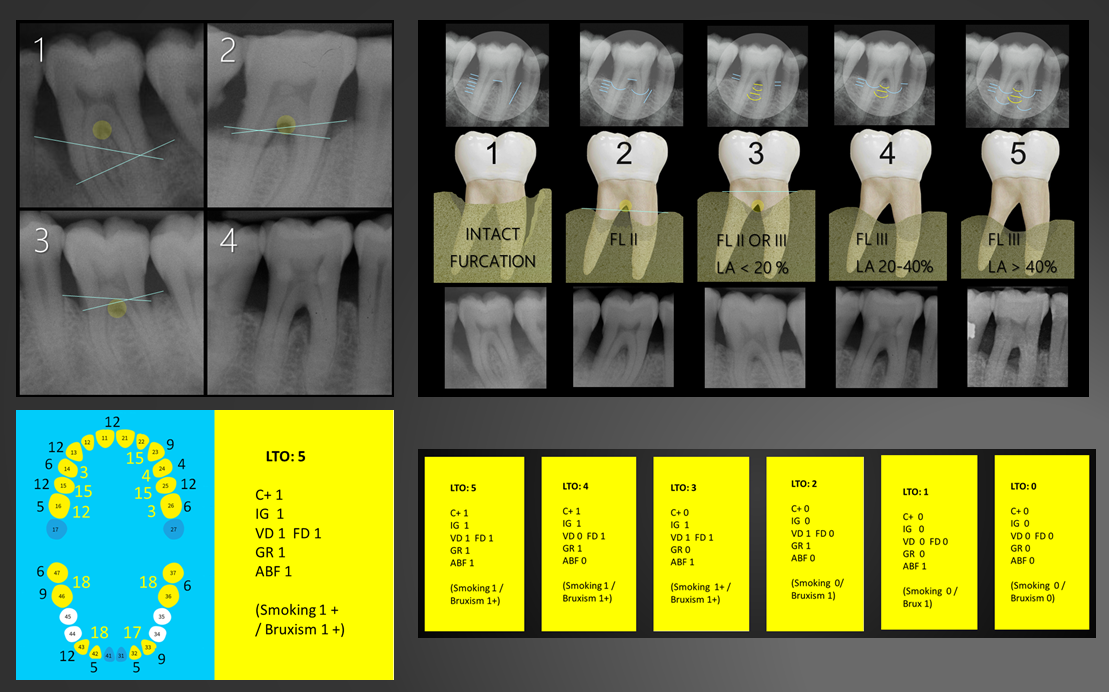

Cerca de 20 factores predictivos de pérdida dentaria se analizaron con diferentes pruebas estadísticas en busca de consistencia de los resultados. Once de estos factores, más claramente asociados con la pérdida dentaria, se seleccionaron finalmente para construir el modelo predictivo.

La idea básica detrás de un modelo predictivo es obtener el valor de probabilidad de pérdida dentaria, un valor de 0 a 1, en lugar de utilizar las categorías pronóstico convencionales, interpretadas subjetivamente en base a los coeficientes de regresión (e.g p. 0.005). Este valor de probabilidad de pérdida puede también asociarse a rangos de expectativa de supervivencia del diente, facilitando la toma de decisiones.

PerioProject no es una herramienta capaz de asegurar que dientes se perderán y concretar cuando, pero sí da valores extremos indicando una alta probabilidad de que el diente se mantendrá (especificidad del 99%) o se perderá, mientras que estima la expectativa de supervivencia para los valores intermedios, dando un significado real al pronóstico reservado convencional.